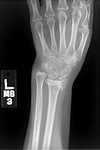

Radiografia posteroanterior mostrando a consolidação viciosa do rádio distal, com encurtamento significativo do rádio e alongamento relativo da ulna

Do acervo do Dr. Chaitanya S. Mudgal